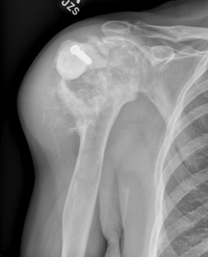

X-rays. Cartilage lesions can often be identified by their radiographic appearance (how they look on an X-ray).

On X-ray:

• Enchondromas have a classic appearance of white “popcorn” calcifications without any aggressive features that would change or damage the surrounding bone.

X-ray of Enchondroma

Benign-appearing cartilage tumor most consistent with enchondroma.